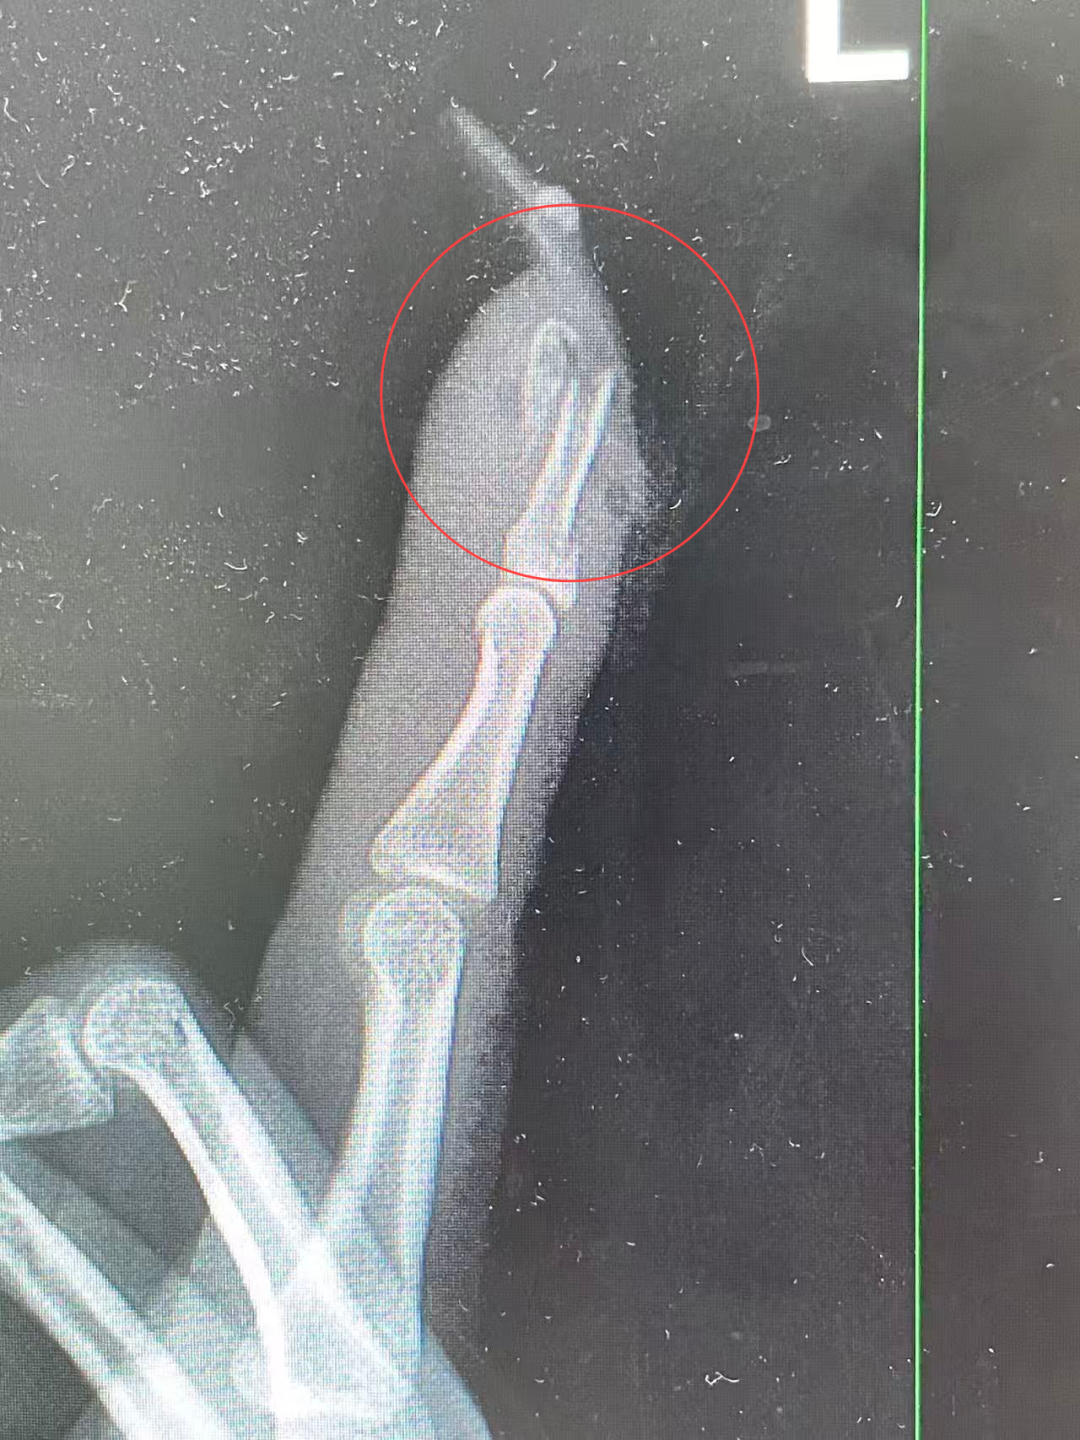

不料,这边才做完美甲,第二天她骑电动车时不慎摔了一跤。手掌本能撑地的同时,一阵钻心的剧痛也随之而来——左手食指上的延长甲片连同甲床直接断裂,鲜血直流。她疼得龇牙咧嘴,立刻前往杭州市临平区中西医结合医院骨科就诊。

“左手食指指骨骨折,甲床破裂,部分甲床外露,需要手术修复。”接诊的曹立副主任医师检查后作出诊断,并当即对其做了指骨骨折闭合复位内固定术。

王小姐术前的X光影像

“如果没有这么细长复杂的美甲,伤害也许不会这么严重。”曹立表示,“延长甲片增加了手指的受力面积和杠杆作用,在摔倒时极易形成‘撬动’效应,导致指甲撕脱、甲床损伤,甚至引发骨折。”